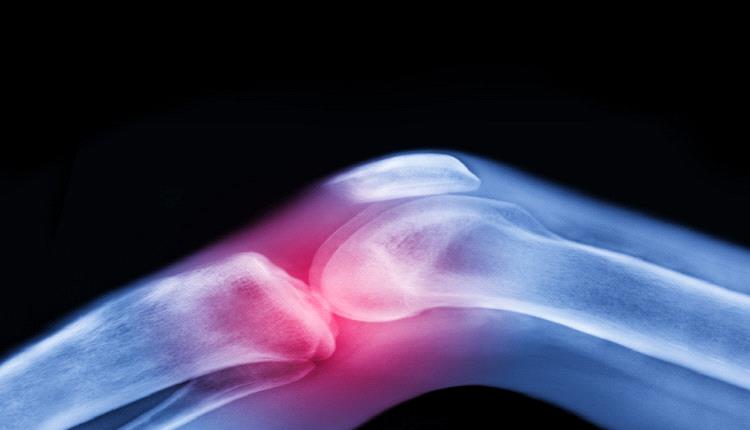

تعتبر آلام المفاصل وتيبّس الركبتين وأوجاع الوركين من الشكاوى الشائعة بين كبار السن، وغالبا ما يُقبل بها كجزء طبيعي من أعراض الشيخوخة.

لكن الواقع الطبي يوضح أن هذا ليس مصيرا حتميا، فالفصال العظمي — أكثر أمراض المفاصل شيوعا في العالم — يمكن الوقاية منه وعلاجه بطرق غير دوائية فعّالة للغاية.

ولا يعتبر الفصال العظمي مجرد تآكل ميكانيكي للمفصل، بل مرضاً يؤثر على جميع مكوناته: السائل الزلالي والغضروف والعظم والأربطة والعضلات المحيطة، وحتى الأعصاب التي تدعم الحركة. وتستهدف الحركة المنتظمة جميع هذه العناصر، وتحافظ على صحة المفصل بكفاءة.

ويفتقر الغضروف، وهو طبقة واقية تغطي أطراف العظام، إلى إمدادات الدم المباشرة ويعتمد على الحركة للبقاء صحيا. فهو يعمل مثل الإسفنجة: ينضغط عند الحركة، فيخرج السوائل ويعيد امتصاص المغذيات، ما يحافظ على مرونة المفصل وصحته.